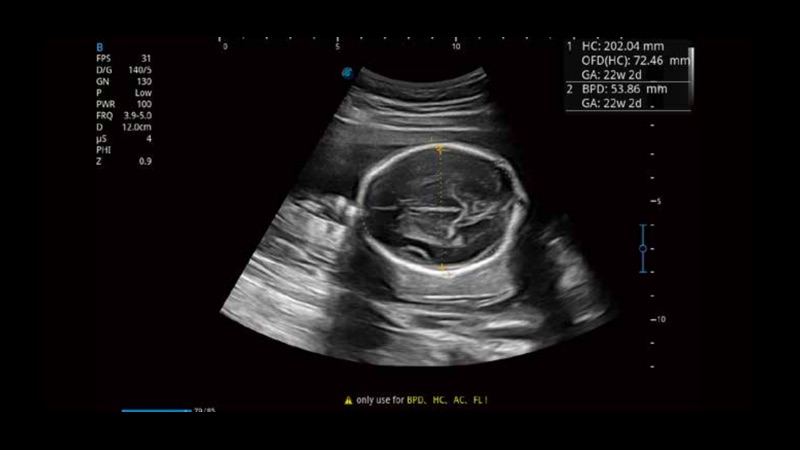

• 产科扫查助手S-Fetus

S-Fetus基于大数据深度学习算法,能够帮助您在产前筛查过程中智能识别胎儿标准切面、自动测量并录入报告。一个按键,即可智能、精准、高效地获取胎儿生理指标,极大简化您的产科检查操作。

• 产科自动测量Auto OB

可快速对产科扫查切面完成胎儿生理学参数的自动测量,减少操作者按键次数,大幅提升检查效率。